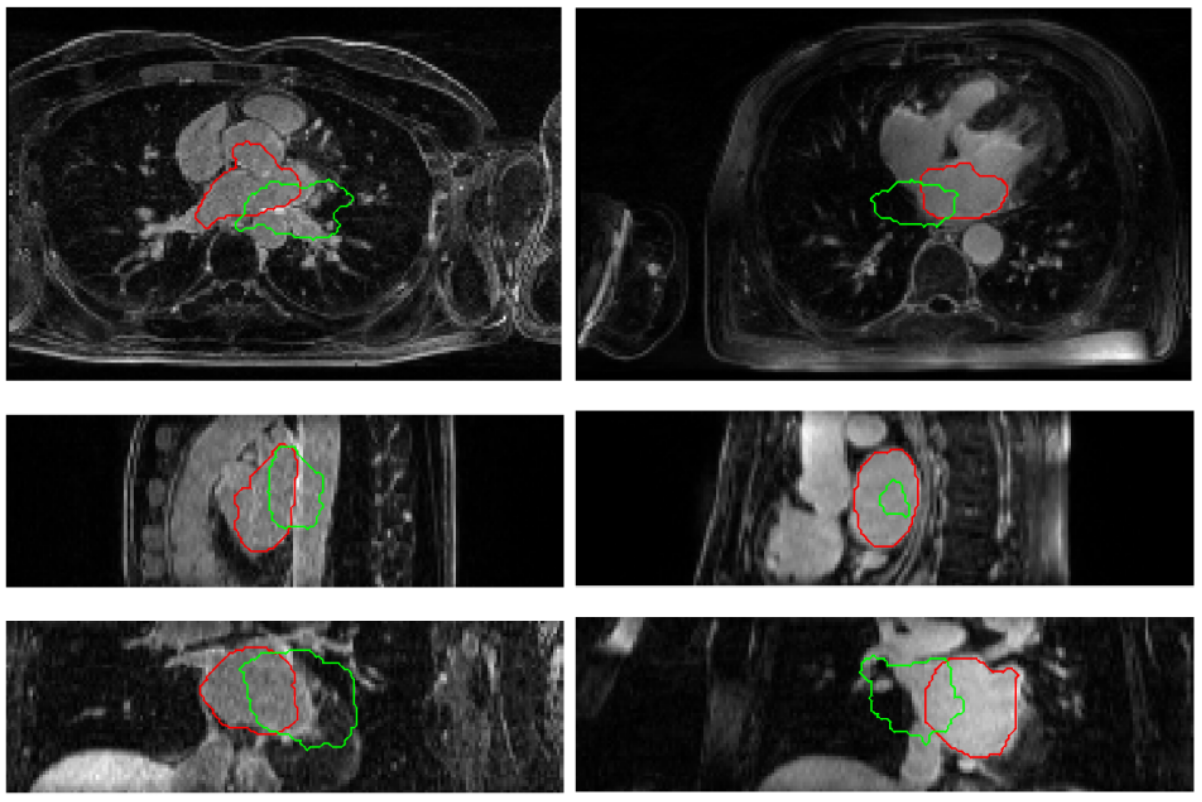

Region-growing process driven by robust statistics and Zernike moments shape prior.

We propose an automatic approach for segmenting the left atrium from magnetic resonance imagery (MRI). The segmentation problem is formulated as a problem in variational region growing. In particular, the method starts locally by searching for a seed region of the left atrium from a given MR slice. A global constraint is imposed by applying a shape prior to the left atrium represented by Zernike moments. The overall growing process is guided by the robust statistics of intensities from the seed region along with the shape prior to capture the whole atrial region.

The proposed method consists of two key steps: (1) search for a seed region of the LA from an image slice in the axial view. (2) explore the LA region using a variational region-growing process. A shape prior is employed to drive the growing process towards atrium-like shapes.